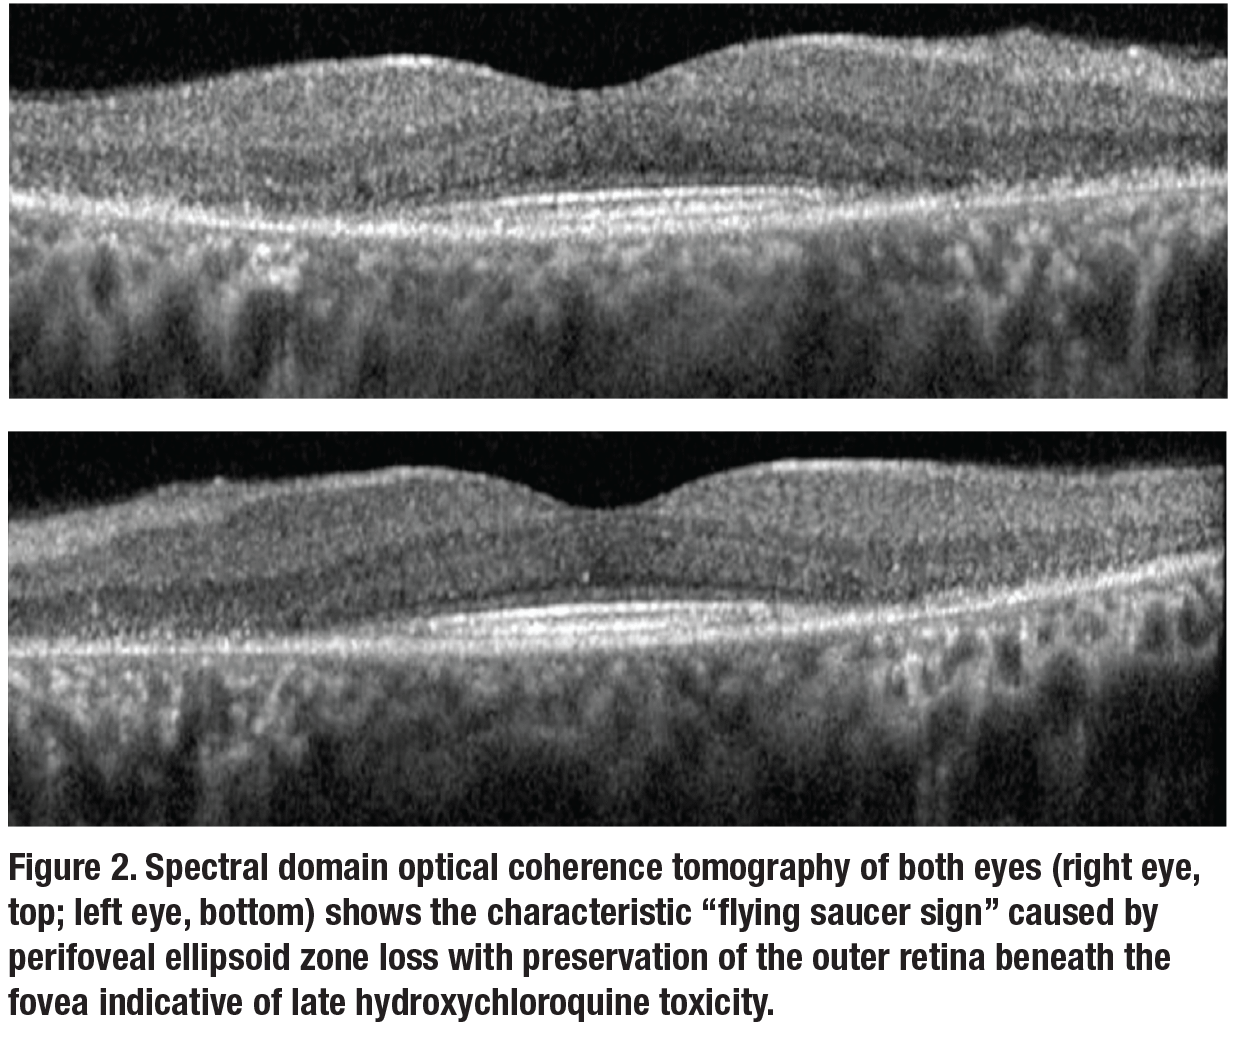

On re-examination, visual acuity was 20/20 and 20/30 in the right and left eyes, respectively. Anterior segment examination was unremarkable. Fundus appearance, spectral domain optical coherence tomography (SD-OCT), fundus auto-fluorescence (FAF) and automated visual fields are shown in Figures 1 to 3.Her medical history was notable for systemic lupus erythematosus (SLE) which was well controlled on hydroxychloroquine (HCQ) for the past 23 years. At her previous visit in 2012, before loss to follow-up, she was noted to have normal retinal morphology and function by multimodal imaging and functional testing.

HCQ retinal toxicity

She was diagnosed with HCQ retinal toxicity, her rheumatologist was contacted and immediate HCQ cessation was recommended. She was switched to azathioprine, and the importance of regular ophthalmologic follow-up was emphasized.